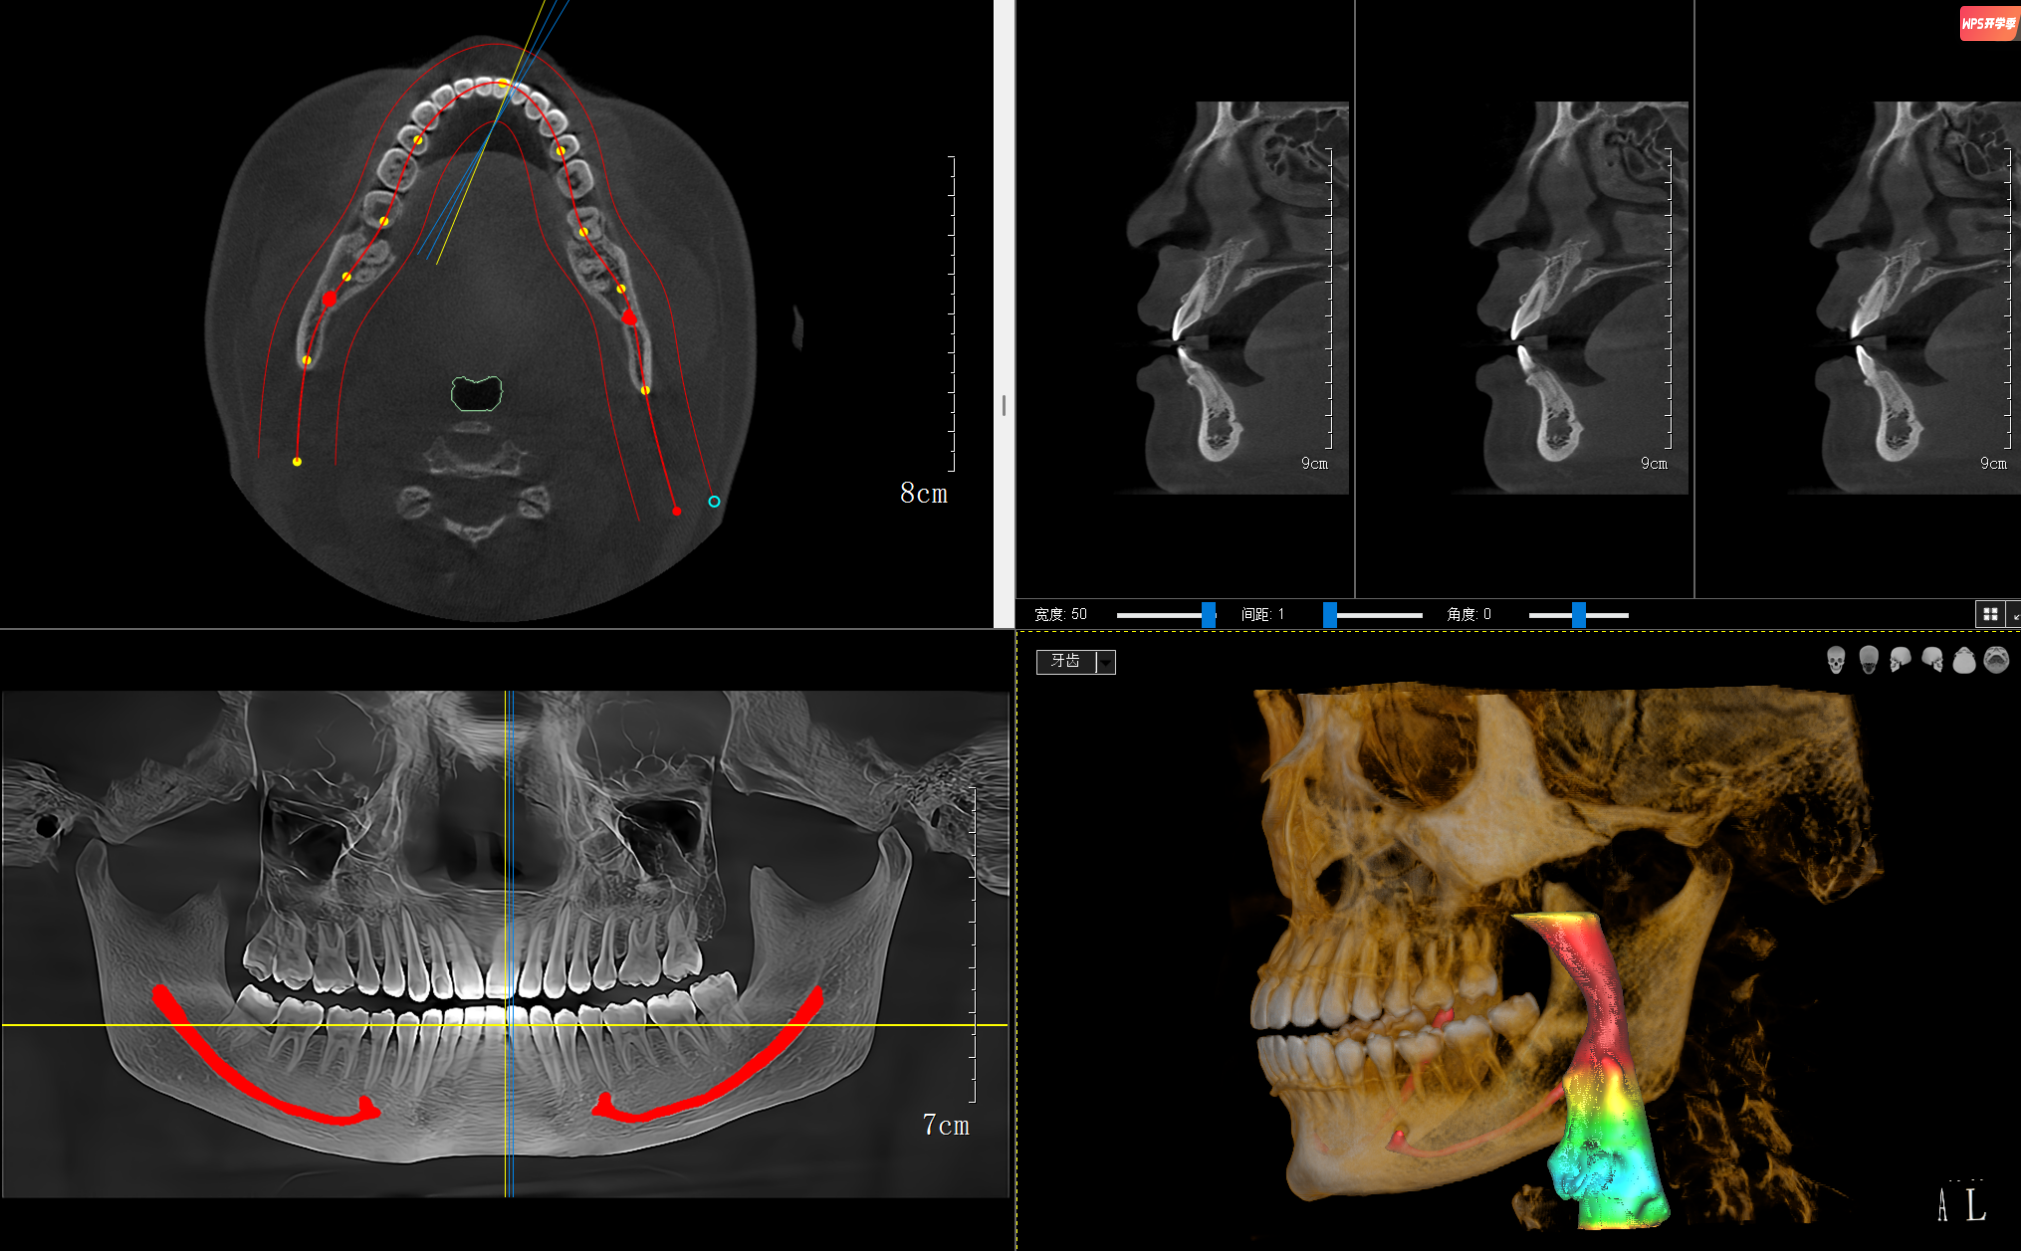

種植牙手術(shù)規(guī)劃:“種牙好比在頜骨中蓋樓”,術(shù)前必須清楚了解“地基”狀況??谇籆T能精確測(cè)量骨頭的厚度、高度、密度,并精確定位神經(jīng)管、上頜竇等重要結(jié)構(gòu)位置,避免手術(shù)損傷神經(jīng)或穿入上頜竇。

臨床研究顯示:使用CBCT引導(dǎo)的種植手術(shù),種植體位置準(zhǔn)確率顯著提高,并發(fā)癥明顯減少。

皓月口腔CT模擬種植軟件截圖

復(fù)雜牙齒矯正:對(duì)于埋伏阻生牙(如常見(jiàn)的阻生智齒)或多生牙病例,口腔CT能確定牙齒在頜骨內(nèi)精確位置、方向以及與鄰牙及神經(jīng)管的關(guān)系,避免拔牙時(shí)誤傷神經(jīng)或鄰牙牙根。

皓月CT自動(dòng)繪制神經(jīng)管、氣道分析